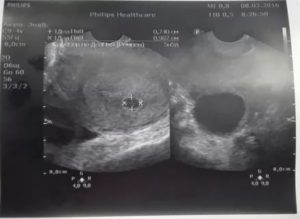

На раннем сроке с 4 по 6 недели срок беременности устанавливают по диаметру плодного яйца. Для этого врач проводит измерение диаметра плодного яйца по его внутреннему контуру в 3 взаимоперпендикулярных плоскостях.

4 неделя беременности на УЗИ. Многоплодная беременность.

Беременность 7 недель